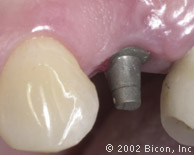

5. | 将一个5.0mm x 8.0mmHA表面的种植体植入。 |